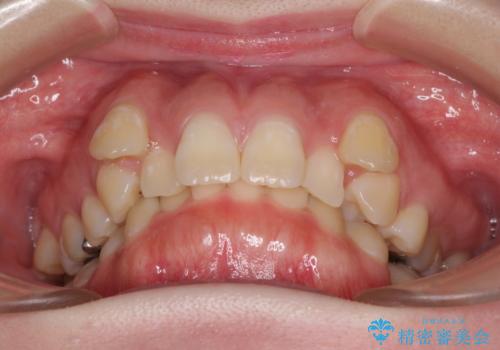

著しい八重歯を短期間で改善 ワイヤー装置による抜歯矯正

- 八重歯と下顎小臼歯の欠損を気にして来院された患者様です。

下顎小臼歯の欠損により過蓋咬合となっていたため、下顎は臼歯を起こすことで咬み合わせを改善し、八重歯は第一小臼歯2本を抜歯し、補助装置を使用して速やかに改善することとしました。

著しい過蓋咬合の改善が必要であった割には、治療期間は2年強と標準的でした。

八重歯は3,4か月で速やかに改善されました。